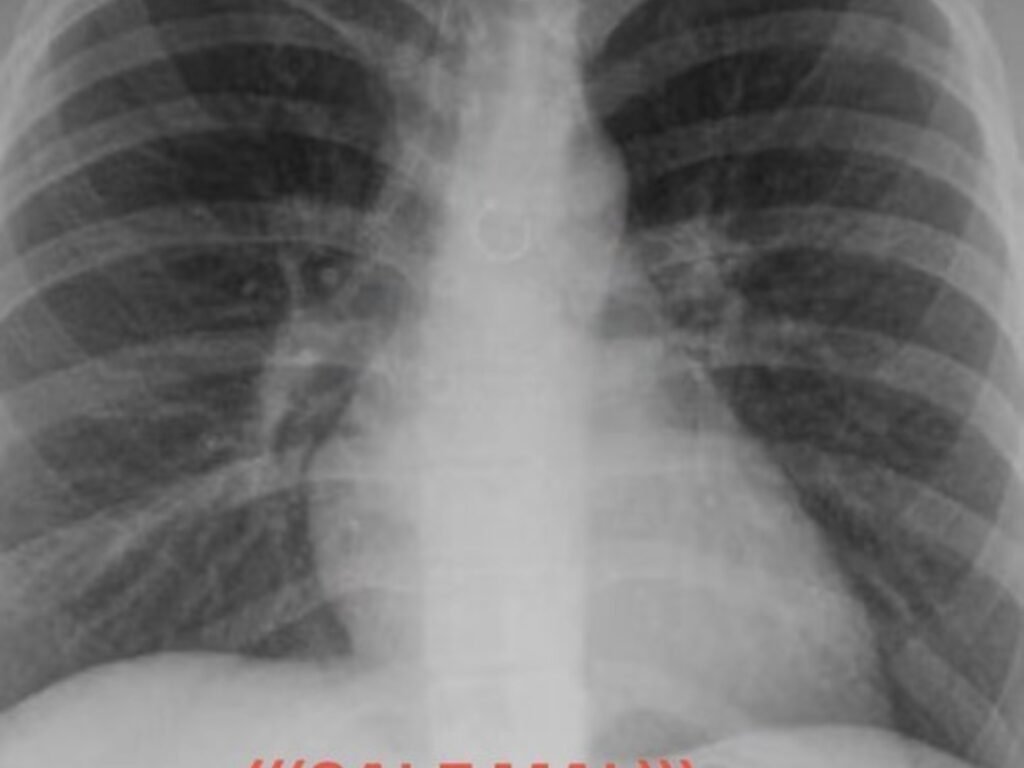

Uncategorized Empezó a toser y un mes después descubrió que tenía un piercing nasal en uno de sus pulmones: "Los médicos estaban impactados" adminhace 2 semanasMenos de 1 min3,0 Vistas Una joven reveló una impactante experiencia personal vinculada a un problema de salud. Acciones: TE RECOMENDAMOS Uncategorized Los dos hombres más buscados por EE.UU.: ofrecen U$S 25 millones por cada uno hace 3 meses Uncategorized Mariano Ojeda, el médico argentino que viajó a África para operar gratis a más de 100 chicos: "Me hicieron sentir que servía para algo en la vida” hace 2 meses Uncategorized Dólar blue hoy: a cuánto cotiza este domingo 22 de febrero hace 2 meses Uncategorized Andrea Bocelli Is Ready to Share the ‘Paradise’ of Opera with the Mexican People hace 4 días Uncategorized John Cena Says There Are ’70 Lost Tracks’ From Recording His 2005 Album ‘You Can’t See Me’ hace 4 meses